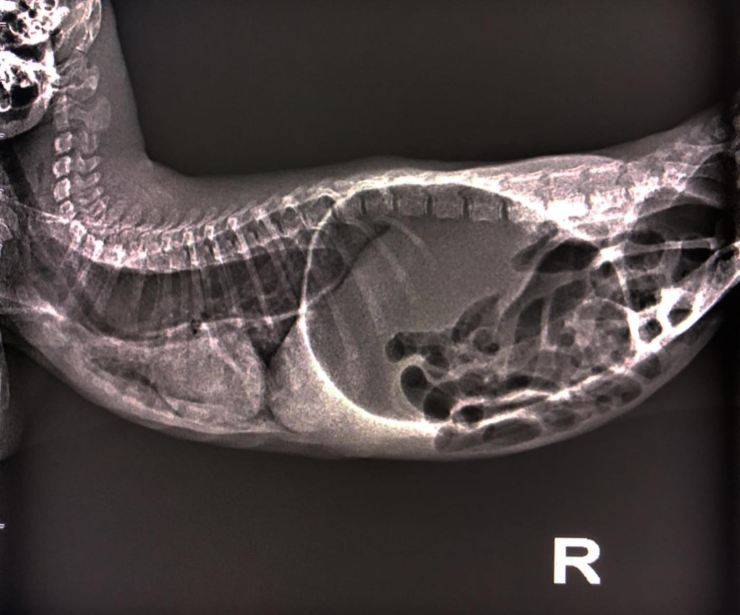

I medici veterinari che l’hanno visitata hanno subito notato uno stato di ipotermia e ipoglicemia e hanno dunque deciso di svolgere subito degli esami più specifici. Dallo studio radiografico è emerso che durante i tentativi di uscire dal water il felino aveva ingerito molta acqua e molta aria e che dunque vi erano i segnali evidenti di megaesofago e polmonite ab ingentis.